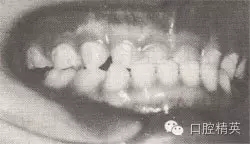

患者,男,4歲,乳牙。磨牙近中關(guān)系。前牙反頜,下頜前突,位置前移。

診斷:乳前牙反頜,安氏Ⅲ類,毛氏Ⅱ¹。

矯治設(shè)計(jì):上頜頜墊式活動(dòng)矯治器。下頜后退位解剖式頜墊,舌簧推乳上切牙向唇側(cè),調(diào)磨頜墊。

治療時(shí)間:1.5個(gè)月,乳前牙反頜解除,乳切牙達(dá)到正常覆頜、覆蓋。下頜回到正常位置。

圖8-37 安氏Ⅲ類錯(cuò)頜,乳前牙反頜矯治前后面頜像

矯治前面相

矯治前咬合圖